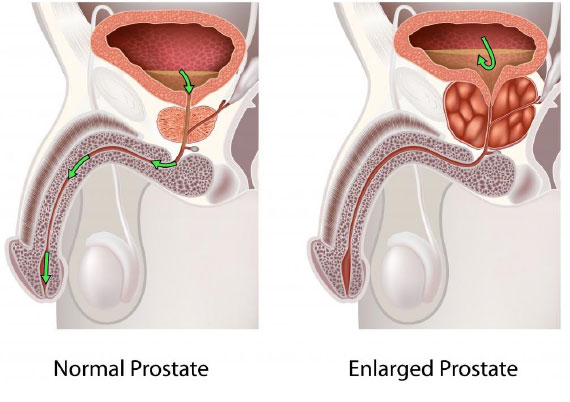

BPH explanation and diagram

The prostate is a gland that sits at the exit of the bladder. In a young man it is 15-25 cc in volume. Imagine it as a ring donut, with urine passing through the donut hole in the centre. As one grows older, the donut often enlarges, and the hole at the centre closes off, obstructing the flow of urine. This happens most commonly due to a benign process where abnormal tissue growth expands from the centre part of the prostate, replacing the normal central tissue, and compressing the normal glandular tissue at the edge of the prostate gland. This is termed BPH- Benign Prostate Hyperplasia.

Prostate cancer, if present, tends to form at the periphery of the gland, and is not often the cause of urinary symptoms. It can however occur together with BPH.